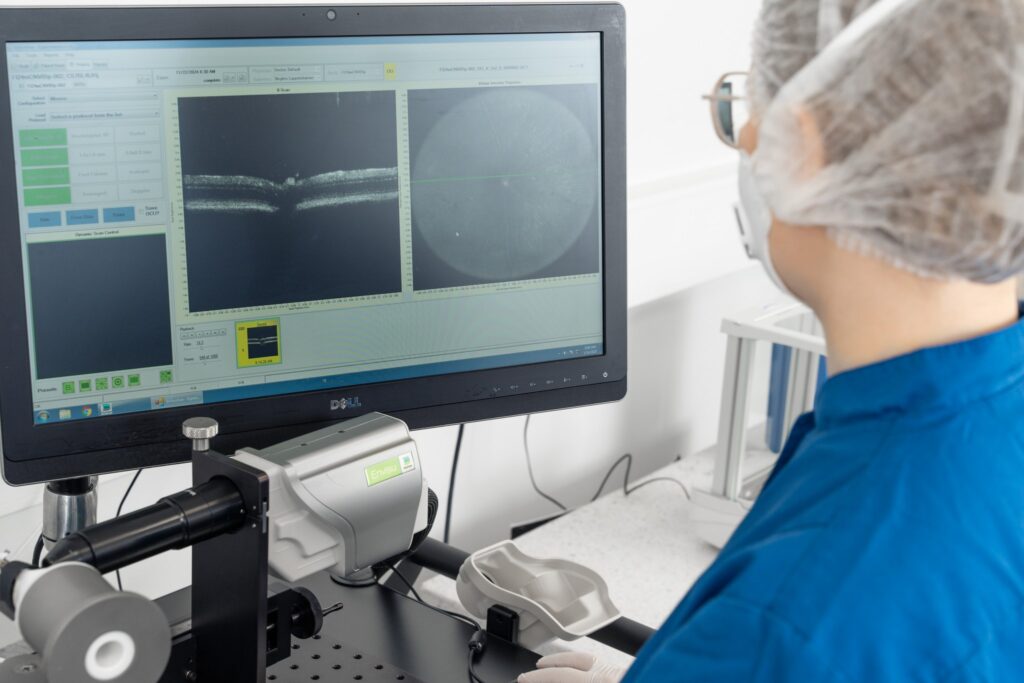

Advances in in vivo imaging, such as fluorescein angiography and optical coherence tomography, enable real-time tracking of disease progression and therapeutic response in the same animals over time, reducing reliance on terminal endpoints.

Supports longitudinal in vivo imaging

Compatible with advanced imaging techniques (e.g., fluorescein angiography) for noninvasive, time-resolved monitoring of disease, treatment response and relapse.